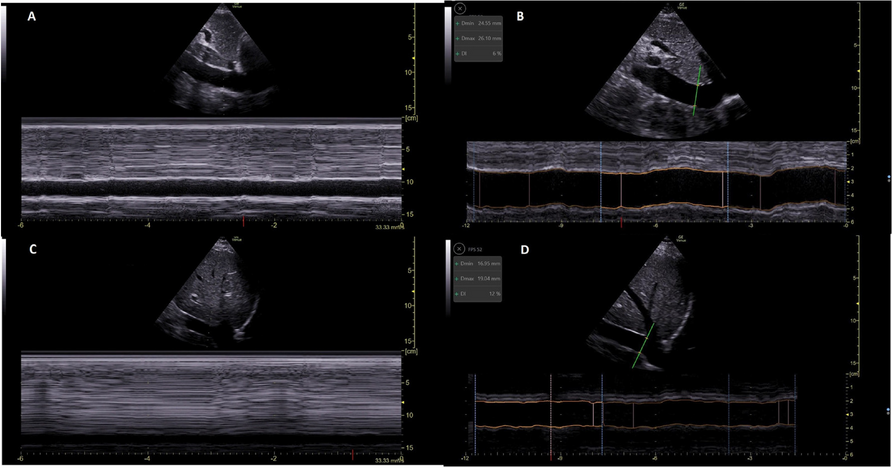

A18 Perioperative cardiocirculatory arrest in a young woman with undiagnosed OSAS: a case report

S. Pilloni, A. Busia, E. Lai, M. Muceli, G. Olla, A. Orru', S. Paba, A. Paddeu, M.V. Piroddi, S. Serdino, A. Usai, F.M. Loddo

Ospedale nostra signora della mercede - SC Anestesia E Rianimazione - ASL Ogliastra, Lanusei, Italy

Correspondence: S. Pilloni

Journal of Anesthesia, Analgesia and Critical Care 2023, 3(Suppl 1):A18

Background. Obstructive sleep apnea syndrome (OSAS) is a frequent pathology: it is estimated that 25% of all patients admitted for elective surgery suffer from OSAS and that more than 80% of them are unaware of it. OSAS is known to be responsible of serious postoperative complications, especially respiratory and cardiovascular, including deaths that are often referred generically to cardiac arrest.1 Guidelines propose decision-making flow charts to manage the most critical aspects of the perioperative path, guiding the screening and identification of patients with suspected OSAS and guiding the planning of pre-, intra- and post-operative care levels.2

Case report. A 35-year-old female with grade I obesity (BMI 35.5) and no other comorbidities underwent videolaparoscopic cholecystectomy. The medical history did not report neither snoring nor daytime sleepiness, and the STOP-Bang questionnaire showed a mild risk for OSAS (score 3).

According to the SIAARTI 2019 OSA screening score, she was classified among patients with a mild risk of OSA (score 1), with a BMI > 35 but with gynoid-type obesity, a neck circumference of 37 cm, and a negative SpO2 test (SPO2 >90% in sitting and supine positions). Moreover, the risk associated with the surgical and anesthetic procedures was moderate (interventional procedure under general anesthesia, score 2). Considering these factors, the risk to be attributed to the patient was to be considered not increased (score 3). After the surgical procedure, the patient was discharged to the ward with SpO2 monitoring, and about 10 minutes after discharge she undergoes cardiocirculatory arrest caused by respiratory arrest. ROSC was obtained rapidly and recovery of consciousness as well, without neurological deficits. On the first postoperative day, episodes of arterial desaturation during sleep were observed, and, in the suspicion of OSAS, pneumologist indicated a polysomnography that confirmed a severe OSAS.

Conclusions. STOP-Bang questionnaire is a good screening tool, but it does not identify all undiagnosed cases of OSAS. Therefore, even in patients at not-increased/low risk for OSAS, the measurement of SpO2 is useful during the post-operative time especially if the risk associated with the surgical and anesthetic procedures is moderate/high. In these situations, the increased levels of analgesia/sedation can have a negative impact on predisposed patients.

Informed consent to publish had been obtained.